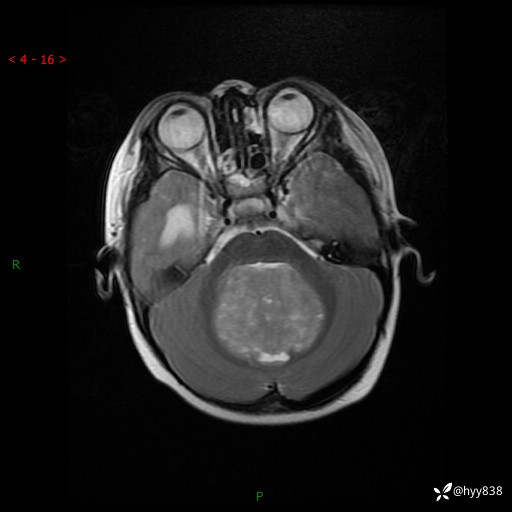

性别:女

年龄:3岁

简要病史:发现行走不稳2个月,加重1个月

颅脑MRI平扫+增强

三脑室、四脑室多发病变,如何分析?